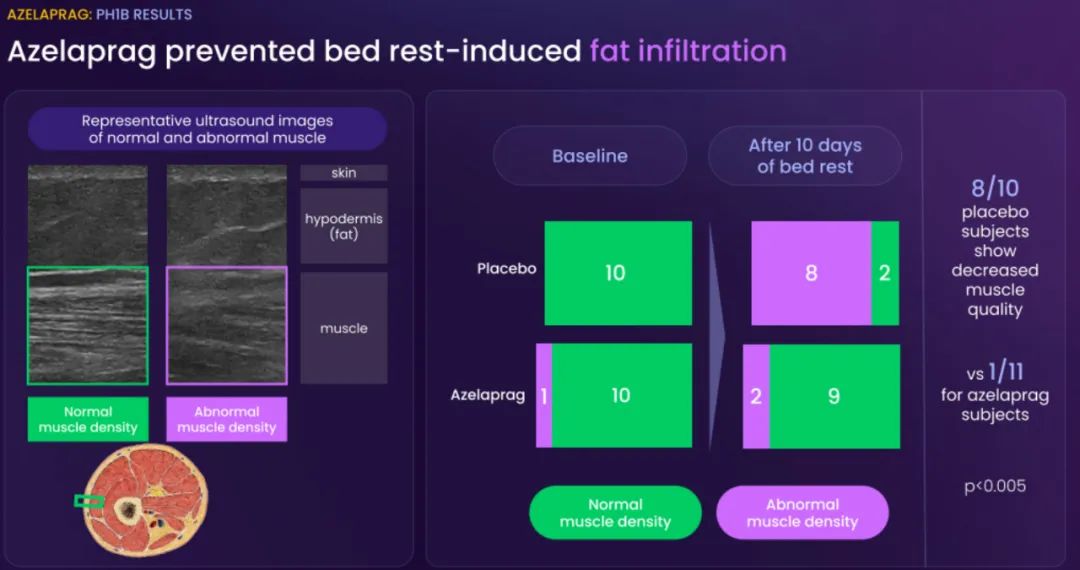

BioAge Labs的主要关注点是代谢疾病,这是全球最大的医疗保健挑战之一。BioAge Labs的主要候选产品 Azelaprag是一种口服小分子,在8个 1 期临床试验中,265 名受试者的耐受性良好。在临床前肥胖模型中,azelaprag 显示出能够使胰高血糖素样肽-1 受体 (GLP-1R) 激动剂诱导的体重减轻增加一倍以上,同时恢复健康的身体成分并改善肌肉功能。

这些临床前结果得到BioAge Labs在卧床老年人中进行的 1b 期临床试验的支持,在该试验中,BioAge Labs观察到在 10 天内接受 azelaprag 治疗的受试者的肌肉萎缩减少、肌肉质量保持良好并且新陈代谢得到改善。